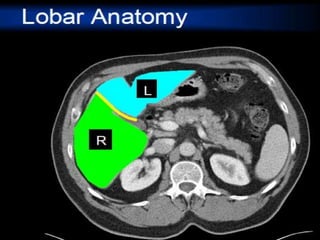

CT cross sectional anatomy.